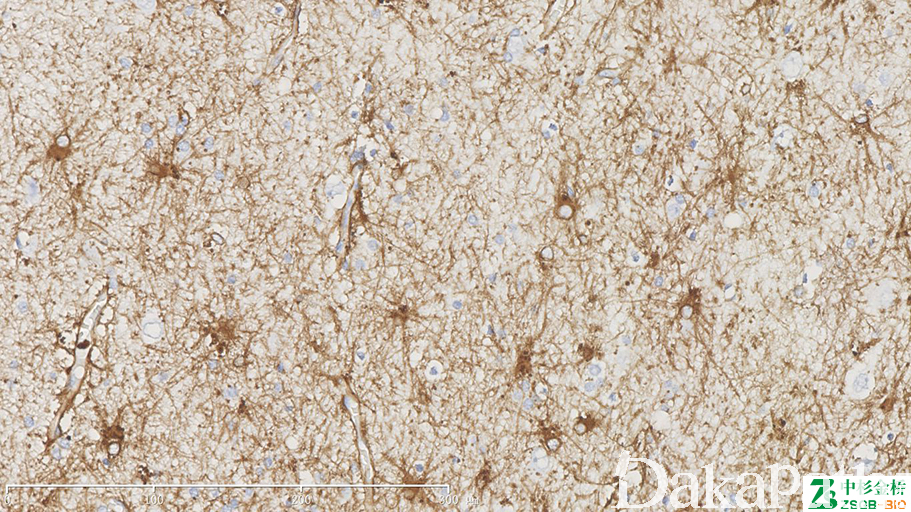

GFAP

别名: Glial fibrillary acidic protein; 神经胶质纤维酸性蛋白

细胞骨架成分,一种中间丝。标记星形胶质细、室管膜细胞及其肿瘤。

信号定位: 胞质

表达于星形细胞、室管膜细胞、视网膜 Muller 细胞,因此可用于这些细胞来源的肿瘤的诊断及胶质瘤与脑膜瘤的鉴别,但不表达于成熟的少突胶质细胞(少突胶质细胞阴性);